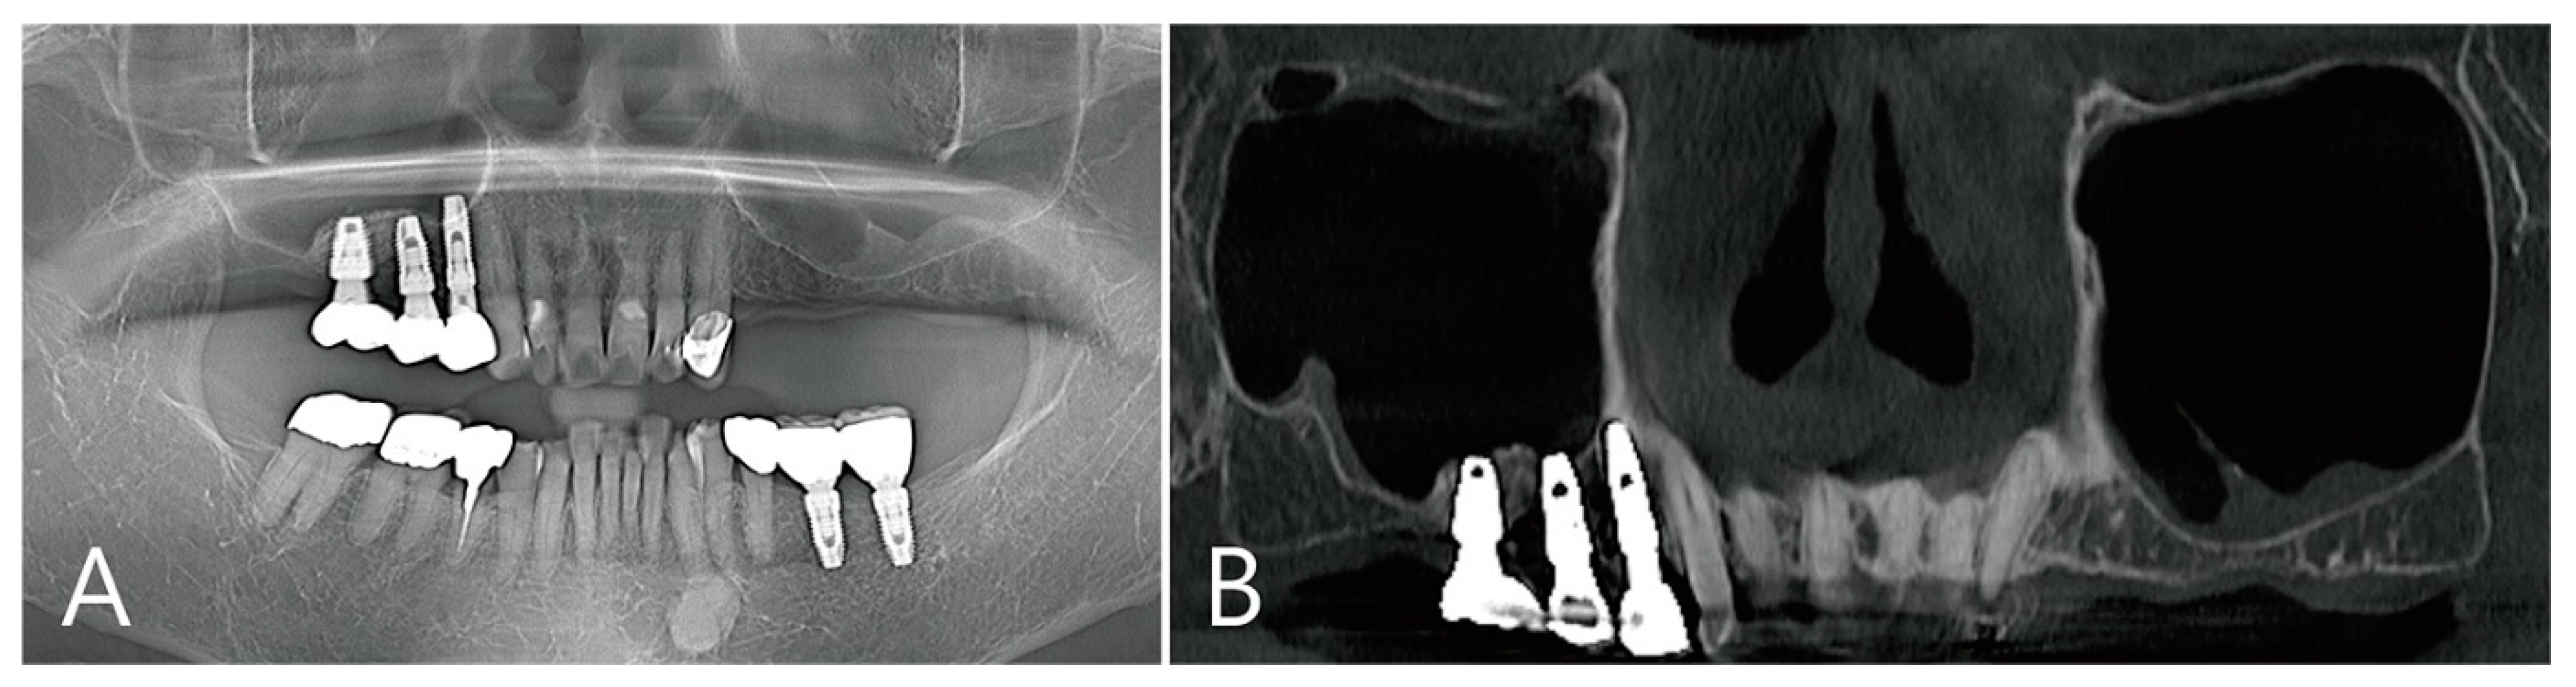

2.5. Case 4

A 75-year-old female who was a non-smoker visited a private clinic to have the implant placed in the edentulous ridge of the maxillary left posterior region (Table 1). This patient was taking antihypertensive and antihyperlipidemic drugs. Preoperative panoramic radiography and CBCT scan were performed. The left maxillary sinus was severely pneumatized and had a minimal residual bone height of 2–4 mm, rendering normal implantation impossible (Figure 10A,B). In the maxillary sinus, membrane thickening was confined to the sinus floor and no sinus pathology was observed in the remaining areas (Figure 10B). Lateral MSA and simultaneous implant placement were planned on the left maxillary sinus.

Figure 10. Case 4. Preoperative panoramic radiography and CBCT scan were performed: (A) the left maxillary sinus was severely pneumatized and had minimal residual bone height; (B) in the maxillary sinus, membrane thickening was confined to the sinus floor and no sinus pathology was observed in the remaining areas.

Figure 13. The coronal image of the CBCT scanned at the #27 implant site was examined: (A) in the image taken immediately after surgery, there was no leakage of bone graft particles; (B) however, a very large grafting void appeared in the image taken one week after surgery; (C) this grafting void showed a cystic appearance in the implant apex, although its size was reduced on CBCT taken after 6 months; (D) in CBCT taken 2 years after the grafting void was removed, the grafting void was replaced with new bone.